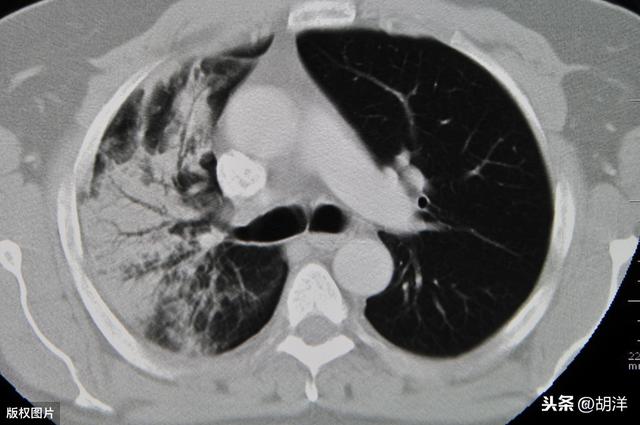

CT是利用人体不同部位对射线吸收的差异,表现出黑白灰不同的高低密度影像。对于肺部疾病CT是最常用的检查方法。应用窗宽技术,肺CT分为肺窗、纵隔窗和骨窗。肺窗主要是看肺内和气管的病变,包括肺内的肿块、结节、感染以及气管的占位或狭窄等。纵隔窗主要是看肿瘤大小或感染实性部分的范围,有无强化,以及与血管的关系,纵隔淋巴结是否肿大,胸腔有无积液,心脏大小及心包有积液等等。骨窗主要是看所扫描的胸部,包含的胸椎以及肋骨,有无骨折及骨质破坏或发育异常。这些地方如果有异常,做了肺部CT平扫及增强基本上一目了然。

不同于其他脏器,肺部含气多,对比度很好,所以肺部CT是判断肺部肿瘤非常好的工具。在肺癌诊疗指南中,肺癌的筛查首选就是低剂量螺旋CT。就拿肺小结节来说,肺部CT可以发现2mm以上的肺部异常小结节,特别是恶性可能很大的磨玻璃结节更加敏感,不但可以清楚的显示肺部结节的发病部位,还能够提供结节内部密度信息,结节的形状,是否有渗透入周围组织生长的迹象,是否有很多血管长在结节周围。此外,肺部CT还可以在计算机里进行三维重建,形成立体图像,对于判断小结节的良恶性非常有帮助。

但是,凡事不是绝对的。你所认为的肺部CT正常是不是一定是正常的?CT机器的分辨率会影响结果的判断,医生的阅片水平也是需要考虑的因素。如果CT机器较老,分辨率低,扫描层厚过大,有可能会使肺部的小病灶被遗漏。如果病灶比较隐蔽,比如在纵膈旁,病灶又较小,这时候不做增强,也有可能被遗漏。此外,一些小病灶,如果医生阅片水平不高,也有可能被忽视。这也是为何不少病人及家属愿意到大医院做检查,并找专家重新阅片会诊的原因。